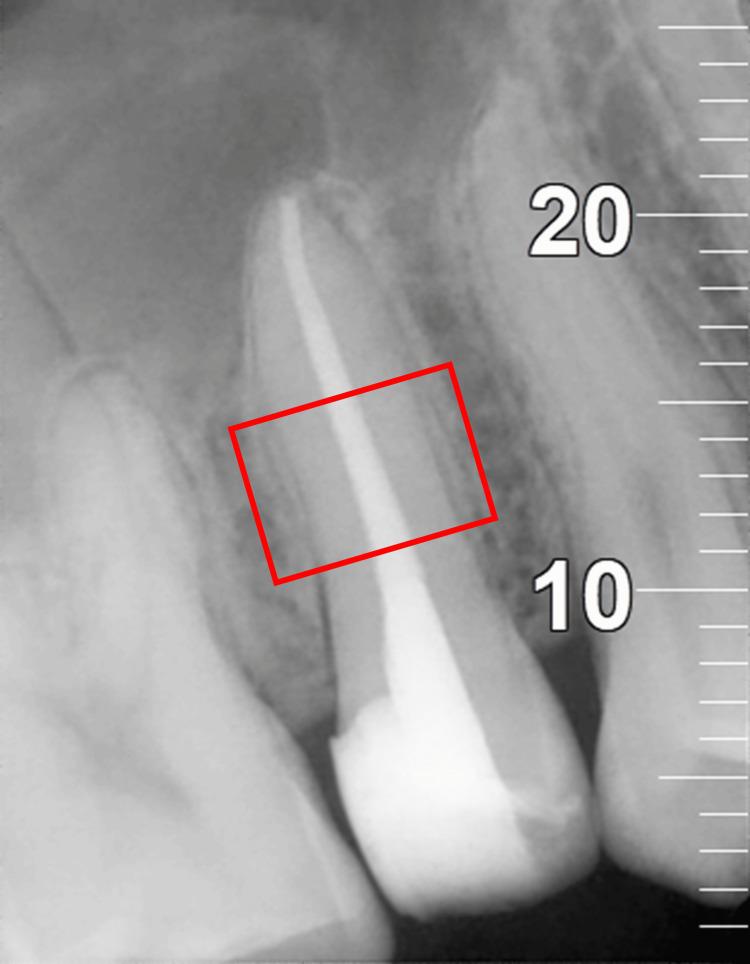

Hundred patients requiring root canal treatment in single-rooted teeth diagnosed with symptomatic irreversible pulpitis, with or without symptomatic apical periodontitis, were recruited. Pre-operative pain levels were recorded using the visual analog scale. Patients were randomized into four sealer groups (Tubli-Seal: Kerr Endodontics, California; AH Plus: Dentsply Sirona, Charlotte; BioRoot RCS: Septodont Healthcare India Pvt. Ltd., Maharashtra, India; and Nishika Canal Sealer BG: Nippon Shika Yakuhin, Shimonoseki, Japan). A single operator performed the treatment in a single visit, using the crown-down technique with Hand Protaper instruments (Dentsply Tulsa Dental, Tulsa), irrigation with 3% sodium hypochlorite (Dentpro, Mohali, India), 17% ethylenediaminetetraacetic acid (EDTA) (MD-Cleanser, EDTA Solution, Meta Biomed, Korea), and distilled water, followed by obturation using the cold lateral condensation technique. Post-operative pain levels were recorded at 24 hours, 72 hours, and seven days. The Kruskal-Wallis H test was employed to compare the pre- and post-operative pain scores across the groups.

Post-operative pain, apical extrusion, and radiopacity showed no statistically significant differences among the four sealer groups (p > 0.05). However, BioRoot RCS had the lowest pain levels at 24 and 72 hours, Tubli-Seal showed the least apical extrusion, and AH Plus and BioRoot RCS exhibited higher and comparable radiopacity.

招募了100例诊断为有症状的不可逆性牙髓炎、伴或不伴有症状性根尖周炎的单根牙需要进行根管治疗的患者。使用视觉模拟量表记录术前疼痛水平。患者被随机分为四个封闭剂组(Tubli-Seal:美国加利福尼亚州Kerr牙髓病公司;AH Plus:美国北卡罗来纳州夏洛特市登士柏西诺德公司;BioRoot RCS:印度马哈拉施特拉邦Septodont Healthcare印度私人有限公司;Nishika根管封闭剂BG:日本下关市日本狮王齿科医药品公司)。由一名操作者在一次就诊中进行治疗,采用冠向下技术,使用手用Protaper器械(美国俄克拉荷马州塔尔萨市登士柏西诺德塔尔萨牙科公司),用3%次氯酸钠(印度旁遮普邦莫哈利市Dentpro公司)、17%乙二胺四乙酸(EDTA)(韩国Meta Biomed公司MD-Cleanser,EDTA溶液)和蒸馏水冲洗,然后采用冷侧方加压技术进行根管充填。在术后24小时、72小时和7天记录术后疼痛水平。采用Kruskal-Wallis H检验比较各组术前和术后疼痛评分。

四个封闭剂组之间的术后疼痛、根尖挤出和不透射线性在统计学上无显著差异(p>0.05)。然而,BioRoot RCS在24小时和72小时时疼痛水平最低,Tubli-Seal根尖挤出最少,AH Plus和BioRoot RCS表现出较高且相当的不透射线性。